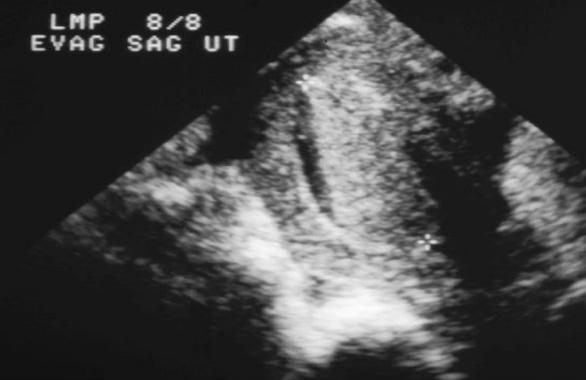

Carcinoma Endometrial

Adenocarcinoma – frecuentes en la etapa

peri y post-menopáusica.

Signo más temprano engrosamiento de endometrio

El diagnóstico es más certero si hay engrosamiento, agrandamiento, alteración del contorno y cambios en la ecogenicidad del endometrio.

Síntomas clínicos:

dolor abdominal o sangrado vaginal (etapa de post-menopausia)

Invade miometrio ( lesiones de ecogenicidad mixta dentro del útero)

La mejor técnica para diagnosticarlo es Endovaginal- muestra cambios en el endometrio y estructuras hipo o hiperecoicas en el miometrio.